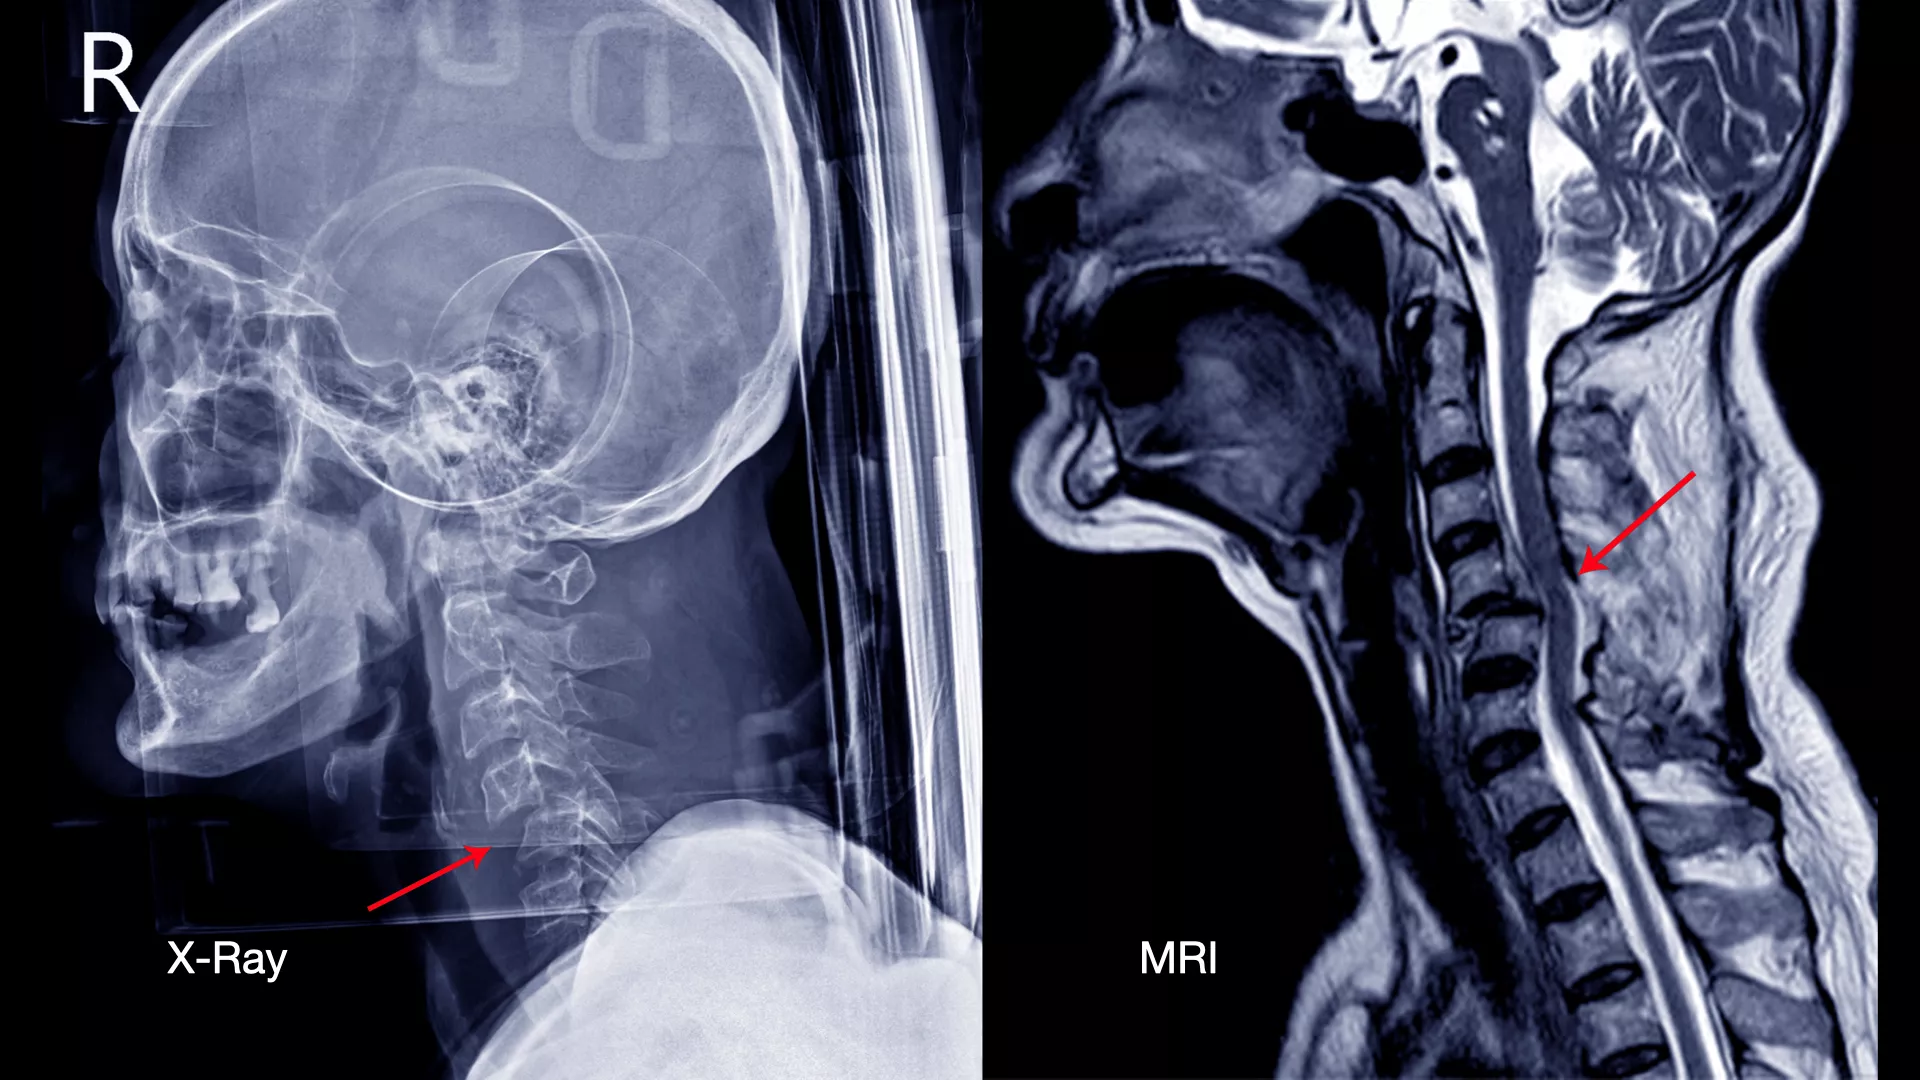

ดังนั้นการตรวจด้วย X-ray ทั้ง 4 ท่านี้จะช่วยให้แพทย์สามารถประเมินโครงสร้างของกระดูกสันหลังได้อย่างละเอียด และเป็นข้อมูลสำคัญในการพิจารณาแนวทางการรักษาที่เหมาะสมสำหรับผู้ป่วยแต่ละราย นอกจากนี้ การตรวจด้วย MRI (Magnetic Resonance Imaging) หรือ การสร้างภาพอวัยวะภายในร่างกายด้วยคลื่นแม่เหล็กไฟฟ้าและคลื่นวิทยุ โดยไม่ต้องใช้รังสีเอกซเรย์ที่เป็นอันตราย ก็มีความสำคัญอย่างยิ่งในการวินิจฉัยโรคกระดูกสันหลัง

X-ray มาแล้วทำไมต้องตรวจ MRI อีก?

การตรวจด้วย X-ray ทั้ง 4 ท่าจะช่วยให้แพทย์ประเมินภาพรวมของโครงสร้างกระดูกได้อย่างละเอียด แต่ X-ray ไม่สามารถแสดงภาพของเนื้อเยื่ออ่อน (Soft Tissue) เช่น หมอนรองกระดูก เส้นประสาท และไขสันหลัง ได้อย่างชัดเจน

ดังนั้น การตรวจด้วย MRI จึงเข้ามาเติมเต็มในจุดนี้ โดยจะะให้ภาพที่มีความละเอียดสูงและสามารถเห็นรายละเอียดของเนื้อเยื่ออ่อนและลักษณะของรอยโรคได้อย่างชัดเจน ทำให้แพทย์สามารถ